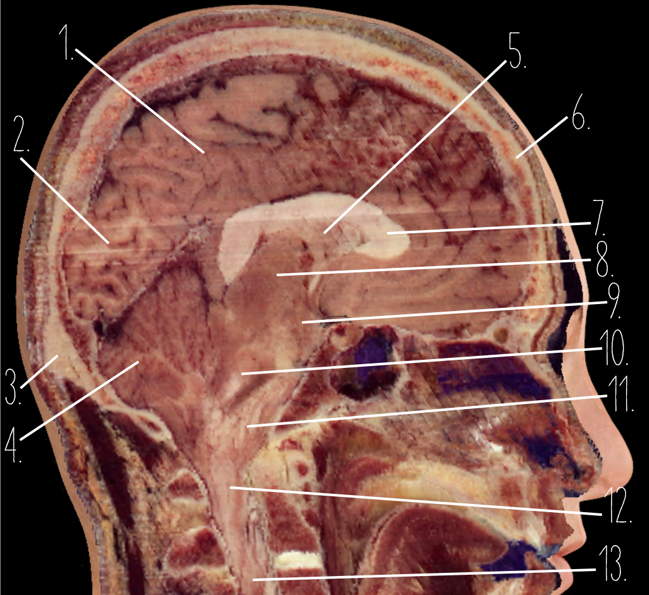

Brain Cross Sectional

1

Frontal Bone

2

Frontal Lobe

3?

Falx Cerebri

4?

Gray Matter

5?

White Matter

6?

Sulcus

7?

Gyrus

8?

Fissure

1?

Parietal Lobe

2?

Cerebellum

3?

Occipital Bone

4?

Cerebellum

5?

Lateral Ventricle

6?

Frontal Bone

7?

Corpus Callosum

8?

Thalamus

9?

Hypothalamus

10?

Midbrain

11?

Pons

12?

Medulla Oblongata

13?

Spinal Cord